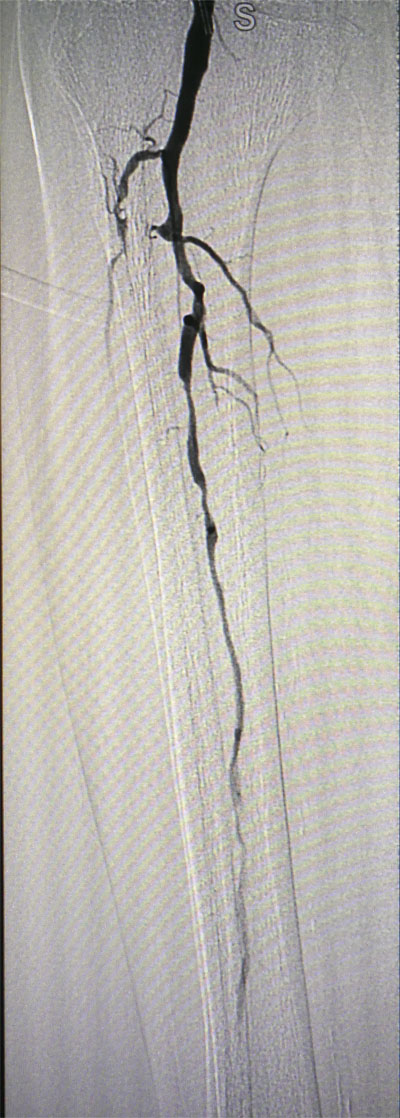

放射科导管室内做好了术前准备,患者由无创呼吸机及各种循环支持下开始介入手术,术中重症监护科严密观察患者的生命体征,内分泌科医生负责手术,患者下肢血流极差,膝下仅存一条多处严重狭窄的腓动脉供血,主要供血的胫前动脉及胫后动脉均长段闭塞,顺行穿刺成功后导丝下行困难,故采用踝下胫后动脉逆穿对接技术成功通过病变。经过近5个小时的奋斗,手术顺利完成,患者腓动脉及胫后动脉血流通畅,血流直达足底动脉环,患者感到足部逐渐温暖,术后清创时患者创面血流丰富。

治疗前